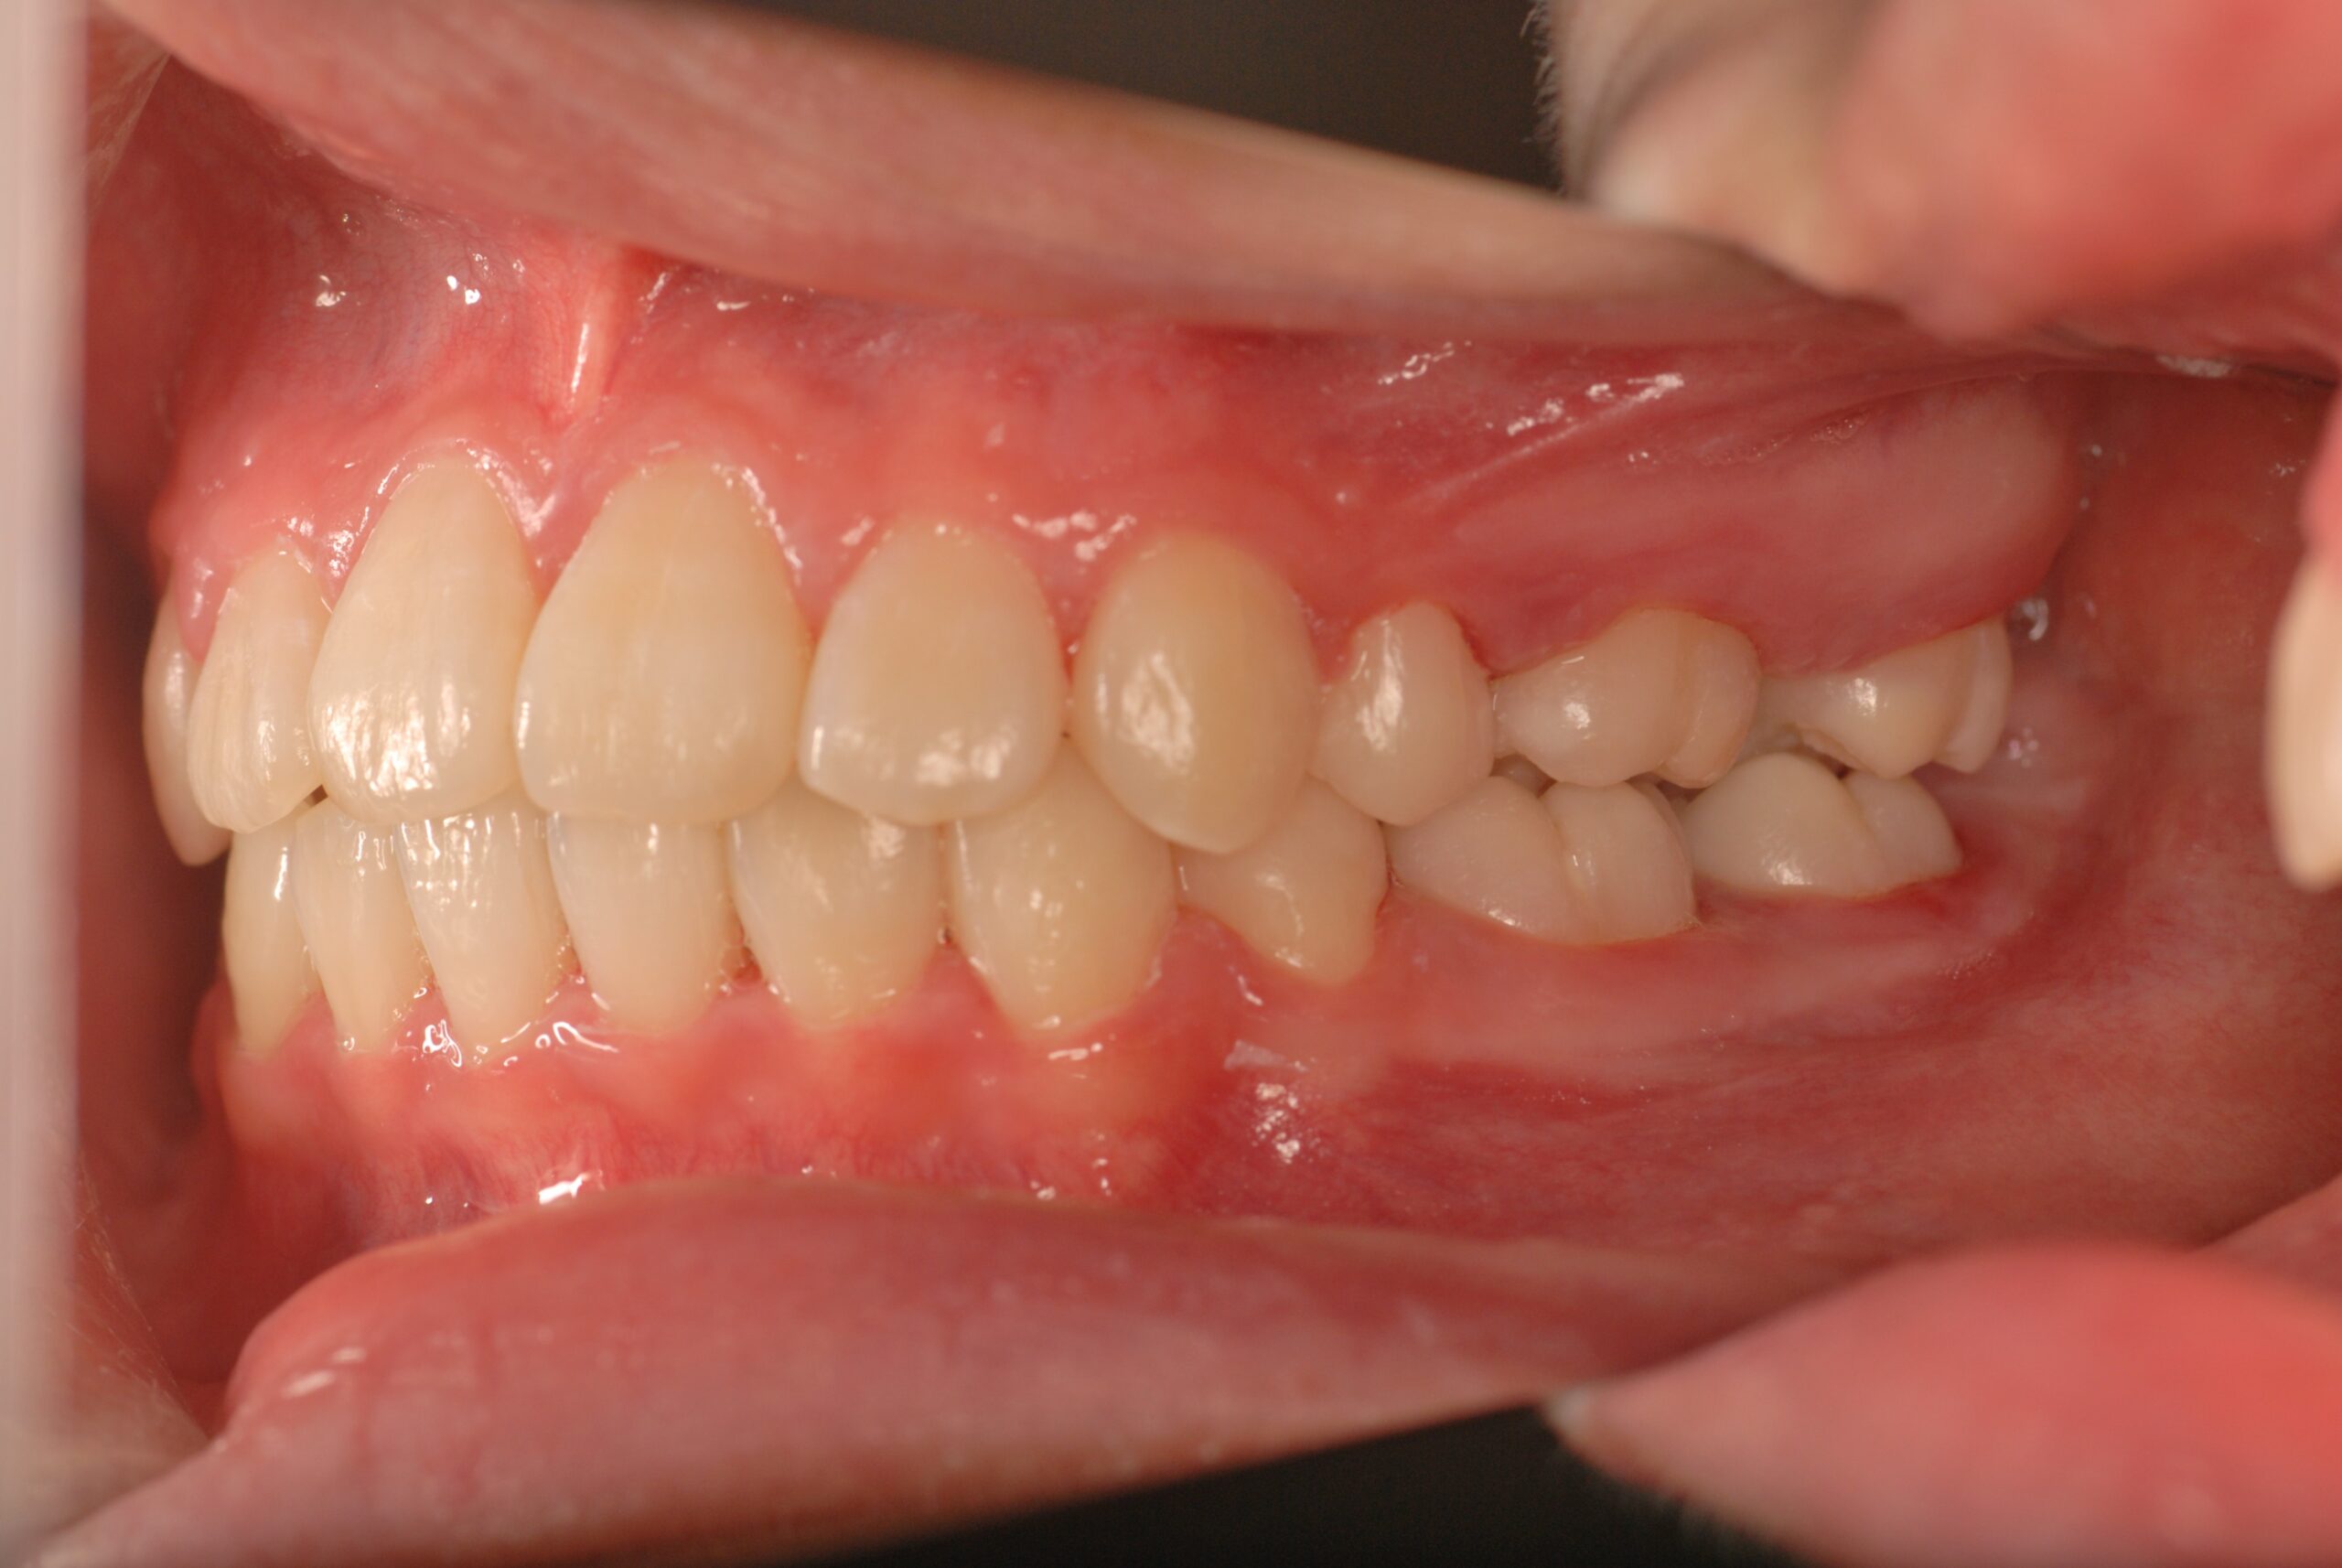

Before

- 診断名、治療内容

- 上顎前突、叢生。 上下顎第一小臼歯を抜歯し、抜歯空隙を利用し、顎外固定装置としてヘッドギヤを併用しながら、上顎前歯を可及的に後退させる。

- 治療期間、費用の目安

- 約3年6か月 約90万円+消費税(検査診断料、矯正料、ヘッドギヤ代、月1回の処置料の総額)